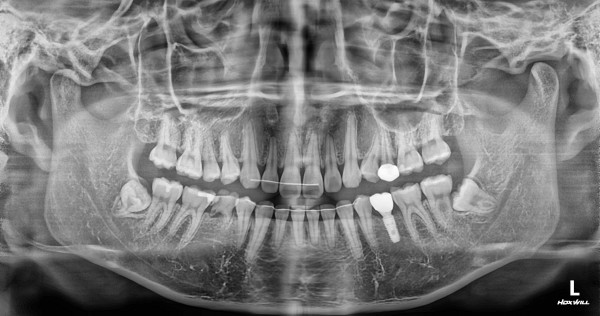

임플란트 센터 | 여) 23세